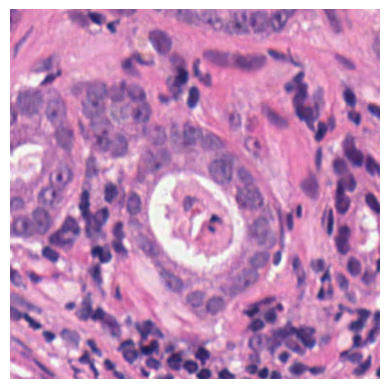

We also analyse the activation maps for each model using GradCAM as described in section S3. This offers more insight into the areas of the image which are contributing most heavily to the models’ representations. In Figure 4(b) we present some representative examples, however, a larger selection which was chosen at random is presented in Figures S10 to S25. The larger selection makes it easier to see the emergent patterns, including that privileged Siamese models tend to mainly identify features which are strongly present in both inputs, while unprivileged Siamese models tend to learn more diffuse features that are not specific to one cell phenotype or image region. TriDeNT ♆ incorporates both sets of features, learning both features specific to the privileged data and more the general features associated with unprivileged Siamese networks.

We can see in Figure 4(b) panel A that for ERG, the privileged Siamese model focuses almost exclusively on any nuclei which could be endothelial cells. As there are very few endothelial cells in the dataset, it could be an effective strategy to identify anything that could potentially be an endothelial cell to minimise the difference between the representations of the H&E model and the IF mask model. In the corresponding unprivileged Siamese image, we see that the model identifies some of these nuclei, albeit less strongly, but also focuses heavily on the other tissue and even the background, while strongly fixating on two spots of debris in the center of the image. This model has less ‘incentive’ to learn the weak features related to endothelial cells as these occur rarely and are not easy to detect, while more generic strong features such as the presence of connective tissue and the prevalence of background are more common and predictable from augmented images. We see that TriDeNT ♆ combines these two feature sets, strongly identifying nuclei while also identifying the connective tissue.

In panel C we see a similar pattern, with the privileged Siamese model fixating solely on the nuclei, while the TriDeNT ♆ model takes a more balanced approach. The unprivileged Siamese model appears to focus on a single cluster of nuclei while neglecting others, and similarly identifies an area of fibroblasts with its distinctive pattern but does not others.

In contrast to panels A and C which represent models with poor privileged Siamese results, panels B and D represent models whose privileged Siamese results were comparable to both TriDeNT ♆ and even the supervised baseline. It is therefore interesting to note that there are far more similarities between the privileged Siamese and TriDeNT ♆ models in both cases. Particularly in panel B, TriDeNT ♆ and the privileged Siamese model return virtually identical heatmaps, with both strongly identifying epithelial nuclei and neglecting the same areas of connective tissue. The unprivileged model in this case appears to focus solely on the centre of the image, giving a significantly different heatmap to the other panels.

Panel D again shows the previous pattern, with the privileged Siamese model identifying the features strongly present in the privileged data – fibroblasts – while neglecting the nuclei present. TriDeNT ♆ also strongly identifies the connective tissue, but, unlike the privileged Siamese model, does not completely neglect the nuclei. The unprivileged Siamese model primarily identifies background, and does not appear to identify the nuclei in this example.